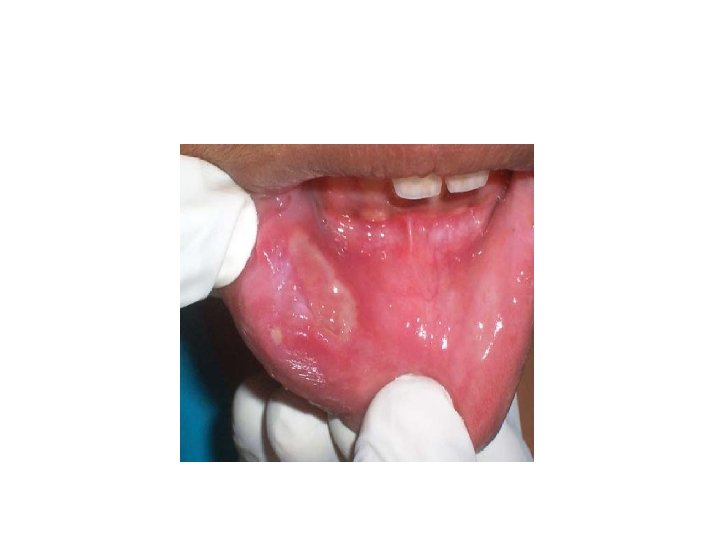

Clinical presentation • Minor Apthae (Mikulicz’s Disease) Ø Most common (80% cases) Ø Fewest recurrence Ø Shortest duration of ulcer episode among the three variants Ø Almost exclusively on non keratinized mucosa Rare on keratinized mucosa Ø 3 -10 mm in diameter Ø Heals in 7 -14 days 1 -5 ulcer /episode

• Major Apthae (sutton’s Disease/ Periadenitis mucosa necrotica recurrens) Ø Larger than minor apthae Ø Longest duration per episode Ø 1 -3 cm in diametyer Ø 2 -6 weeks to heal Ø 1 -10 ulcer /episode Ø Any oral surface may be affected Ø Onset usually after puberty and recurrent episode upto the age of 20 yrs Ø Healing with scaring may leads to a restricted mouth opening

Herpetiform apthae Ø Demonstrate the greatest number of ulceration. Ø May be 100 ulcers/episode Ø 1 -3 mm in diameter Ø Bears superficial resemblance with HSV lesion. Ø Heals within 7 -10 days and reoccur soon